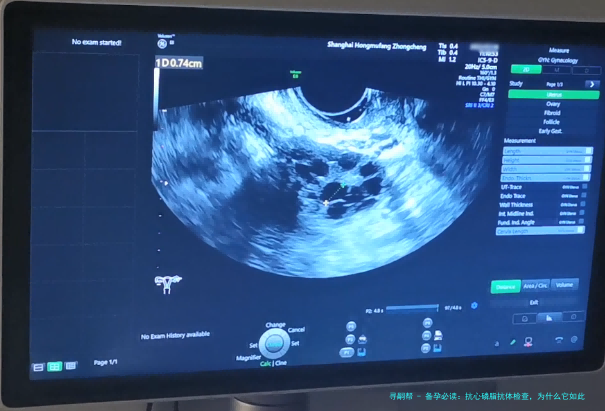

什么是抗心磷脂抗体?它为什么和备孕扯上关系?

首先,抗心磷脂抗体是个啥玩意儿?简单说,它是一种自身免疫抗体,正常情况下,我们的免疫系统是保护身体的“卫士”,但有时候它会“犯糊涂”,攻击自己的细胞,比如攻击血管内皮细胞上的磷脂,导致血栓形成。这听起来有点专业,对吧?但别急,我来打个比方:想象一下,你的身体是一座城市,免疫系统是警察,抗心磷脂抗体就像是“内鬼警察”,它不抓坏人,反而破坏交通(血管),导致“堵车”(血栓)。在备孕中,这种“堵车”会影响子宫的血液供应,让胚胎难以着床或发育,从而增加不孕和流产的风险。